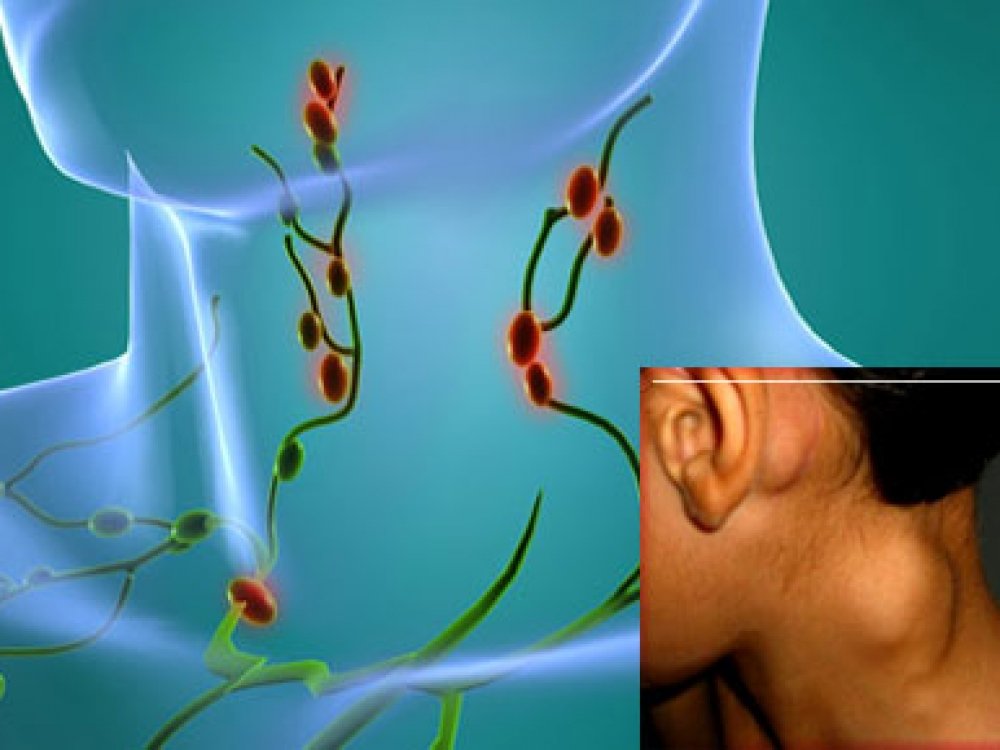

Изображения и схемы: как выглядит лимфа